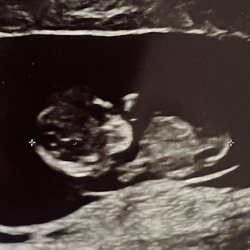

Wellicht zoiets? Vaak bereken je die op basis van je uitgerekende datum